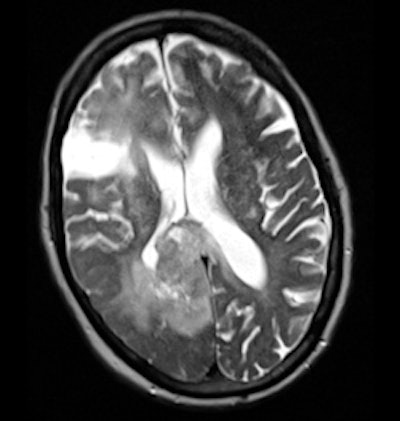

Following further clinical review, it was felt that the presentation was atypical for a cerebrovascular accident (CVA), particularly as the symptoms had been slowly progressive for two weeks. An MRI scan was requested. This demonstrated a large paracentral tumor in the right occipital lobe (figure 2). Review of the CT shows asymmetry of the gray white matter and compression of the ventricle which was not appreciated at the time of initial reporting.

This is clearly an observational error. The referral direct from the stroke unit with clinical information suggesting a CVA may well have introduced a bias toward identifying the abnormalities as ischemic in origin.

Careful interrogation of the image, despite the clinical information, may well indicate causes other than "stroke."